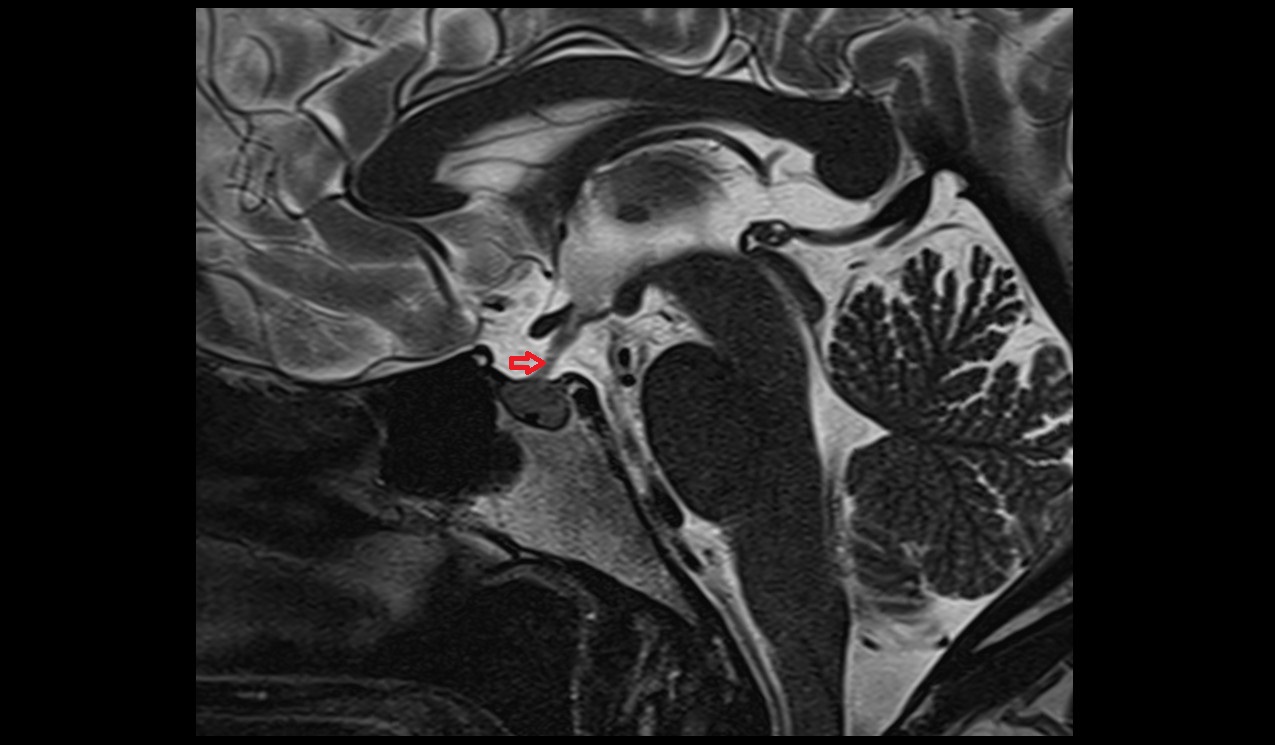

- Meckel’s cave (Trigeminal cave)